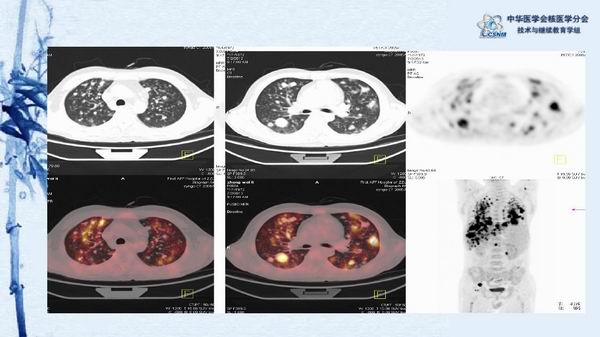

病例49:PET-CT显像诊断淋巴瘤相关噬血细胞综合征一例-【CSNM继教学组】程兵 郑州大学第一附属医院